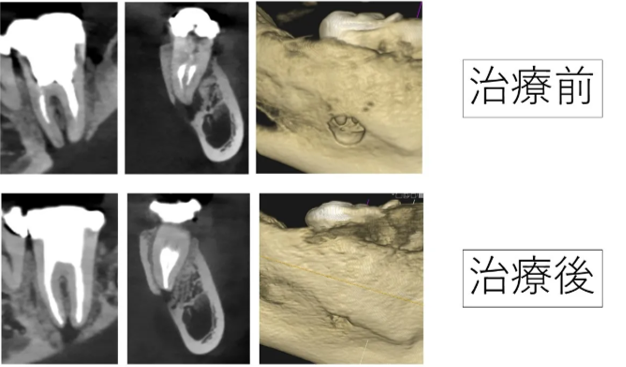

根の大きな病気で骨が溶け穴に。精密な根管治療で骨が再生した症例